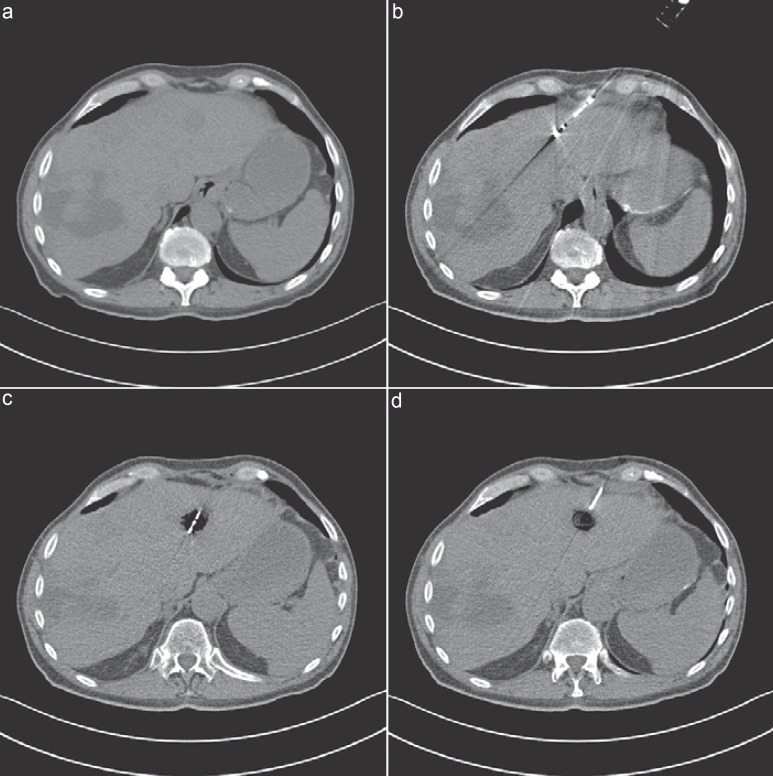

Methods: Liver-directed therapies are classified into vascular transarterial techniques such as chemoperfusion (TACP), chemoembolization (TACE), radioembolization (selective internal radiation therapy (SIRT)), and chemosaturation, as well as thermal ablation techniques like microwave ablation (MWA), radiofrequency ablation (RFA), laser-induced thermotherapy (LITT), cryotherapy, and irreversible electroporation (IRE). The authors searched the database PubMed using the following terms: 'image-guided tumor ablation', 'thermal ablation therapies', 'liver metastases of uveal melanoma', 'neuroendocrine carcinoma', 'breast cancer', and 'non-colorectal liver metastases'.

Results: Various combinations of the above-mentioned therapy protocols are possible. In neuroendocrine carcinomas, oligonodular liver metastases are treated successfully via thermal ablation like RFA, LITT, or MWA, and diffuse involvement via TACE or SIRT. Although liver involvement in breast cancer is a systemic disease, non-responding nodular metastases can be controlled via RFA or LITT. In ocular or cutaneous melanoma, thermal ablation is rarely considered as an interventional treatment option, as opposed to TACE, SIRT, or chemosaturation. Rarely liver-directed therapies are used in pancreatic cancer, most likely due to problems such as biliary digestive communications after surgery and the risk of infections. Rare indications for thermal ablation are liver metastases of other primary cancers like non-small cell lung, gastric, and ovarian cancer.